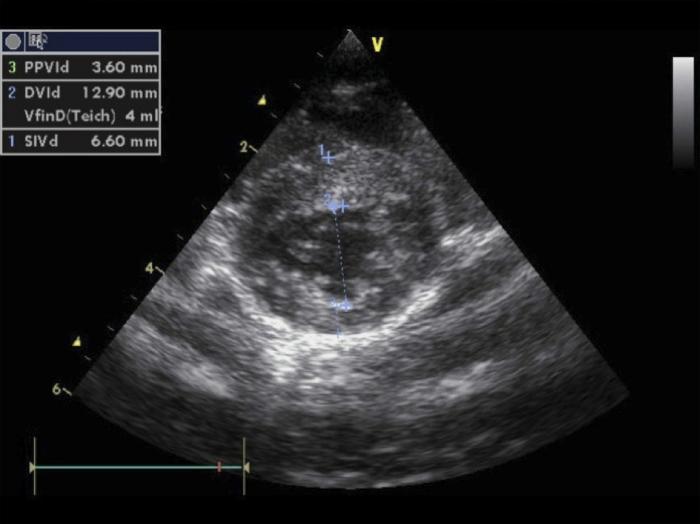

Al mes de tratamiento se realizó una revisión en la que se detectó un soplo cardíaco III/VI. La frecuencia cardíaca era de 240 lpm. En la analítica sanguínea se mantuvo el hematocrito bajo (22.6 %) y los valores de creatinina (3.1 mg/dL) y urea (99 mg/dL) por encima del rango de referencia. Se realizó un NT-proBNP cuantitativo con un valor de 210 pmol/L. (Estos valores se encuentran 100 - 270 pmol/L y el laboratorio de referencia los clasifica como anormales/sospechosos e implican que hay estrés en el miocardio). En ese momento se recomendó realizar una ecocardiografía pero se pospuso por problemas económicos.

Se decidió realizar una ecocardiografía en la que se evidenciaron alteraciones compatibles con una cardiomiopatía hipertrófica obstructiva (Figura 3). Como la frecuencia cardíaca continuaba elevada en 260 lpm, se decidió instaurar un tratamiento con atenolol 6.25 mg/gato una vez al día.